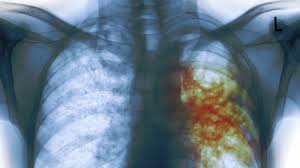

Investigadores argentinos desarrollan nuevos compuestos contra la tuberculosis

Probaron con éxito en laboratorio nuevas drogas que podrían mejorar el tratamiento de una enfermedad que provoca dos millones de muertes cada año..

Investigadores platenses y rosarinos diseñaron y probaron con éxito en laboratorio nuevas drogas que podrían mejorar el tratamiento de cepas resistentes del bacilo que causa la tuberculosis, una enfermedad que provoca dos millones de muertes cada año, informó la Agencia CyTA del Instituto Leloir.